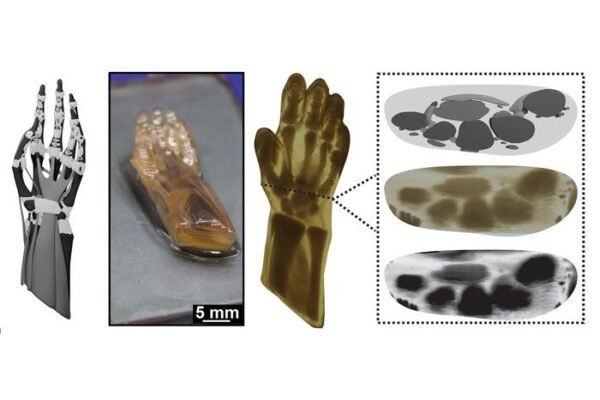

Teksaso universiteto mokslininkai sukūrė metodą, leidžiantį 3D spausdinti žmogaus rankos modelius su įvairiomis savybėmis iš vieno medžiagos šaltinio.